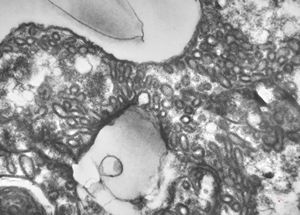

M,50y. | Pneumocystis carinii

M,3m. | Pneumocystis carinii